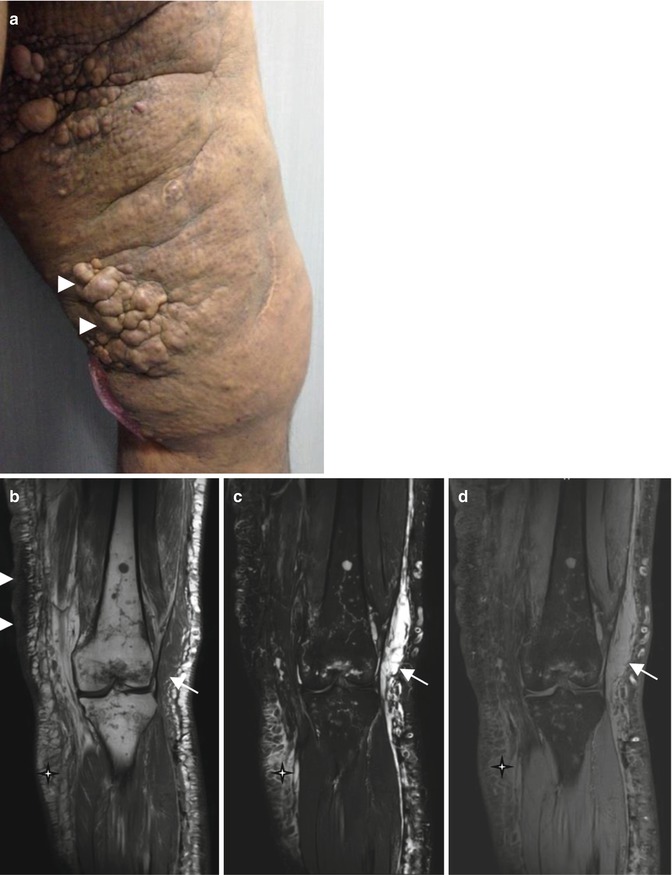

Microcystic lymphatic malformation. (a) Clinical photograph. (b) Coronal T1-weighted MR image. (c) Coronal T2-weighted MR image with fat suppression. (d) Coronal T1-weighted MR image after Gadolinium contrast administration with fat suppression. (a) Clinical photograph shows an extensive skin lesion of the thigh (white arrowheads). (b–d) MRI reveals the skin thickening on T1-weighted image (white arrowhead) (b) and a diffuse involvement of the subcutaneous tissue (star) with a lobulated and septated mass (arrow). There is no significant enhancement of these features (d), a finding characteristic of a microcystic lymphatic malformation. Note the associated involvement of the bone